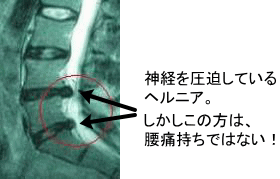

〝椎間板がつぶれ、

神経が圧迫されている…”

…↑こんな状態の写真を見せられたら、多くの方が不安な気持ちになる事と思います。

何しろ画像で、飛び出したヘルニアに神経が圧迫されているのを見てしまったわけですから。